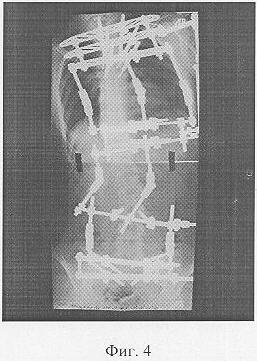

Фиг.4 – копия рентгенограммы после коррекции.

После этого на операционном столе приложили разнонаправленные усилия P1, P2 во фронтальной плоскости на вершине искривления и у каудального основания сколиотической дуги. При этом разнонаправленные дозированные усилия направляли к центральной оси тела человека. Вдоль центральной оси тела человека прикладывали пару разнонаправленных дополнительных усилий в краниально-каудальном направлении.

В послеоперационном периоде выполняли спондилограммы, на которых измеряли углы деформации и определили темп и длительность дальнейшей дозированной коррекции. При этом контрольные спондилографии выполняли по мере необходимости.

После достижения максимально возможной коррекции деформации позвоночника осуществили спондилодез.